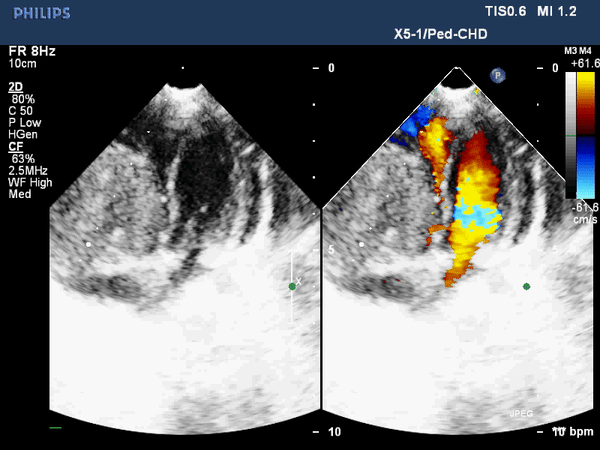

Выполняется трансторакольное ЭХОКГ исследование, которое позволяет заподозрить локализацию и размер опухоли, ее соотношение с другими анатомическими структурами сердца.